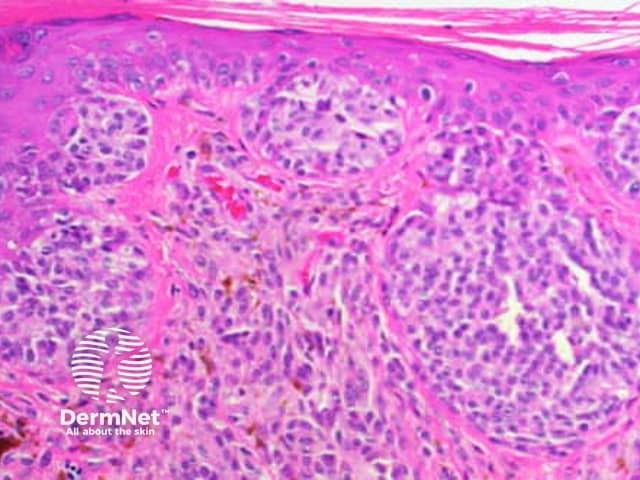

Histological features of invasive squamous cell carcinomas can vary, but in general are:

Pathology of invasive squamous cell carcinoma

Pathology of squamous cell carcinoma keratinisation